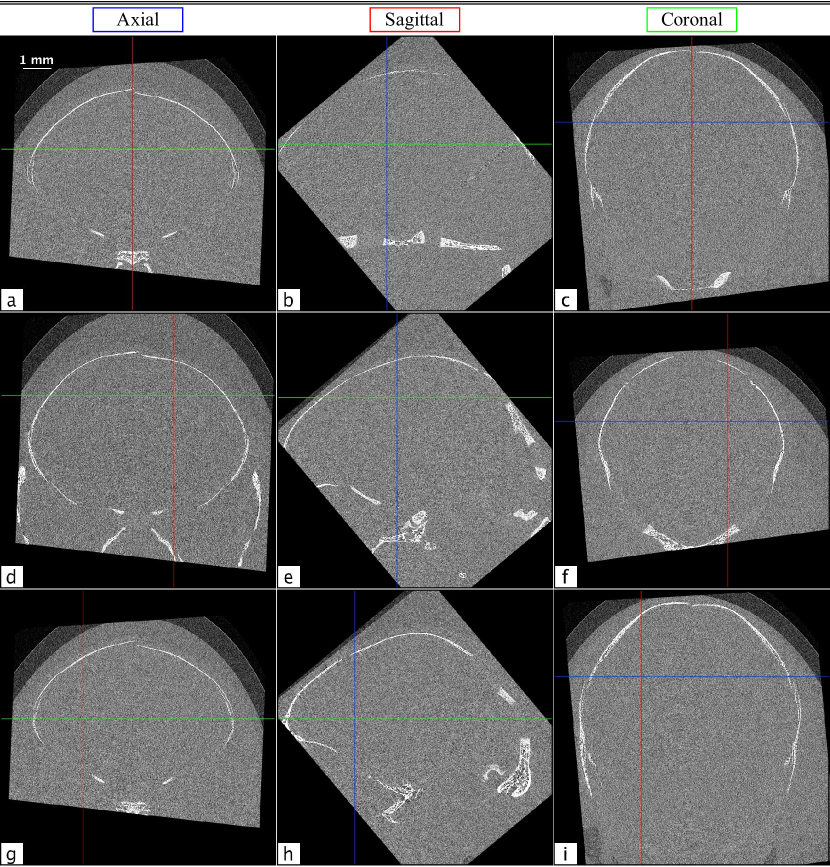

Rabbit kitten brain CT

The full volume of the in situ rabbit kitten data set was reconstructed using filtered back projection (FBP) and rotated to create axial, sagittal, and coronal views for both absorption contrast and phase retrieved PBI CT (Δδ/Δμ=5.66×1010Δ𝛿Δ𝜇5.66superscript1010\Delta\delta/\Delta\mu=5.66\times 10^{-10}). Several slices of the absorption contrast CT volume can be seen in Fig. 7. The views are denoted in blue, red, and green for axial, sagittal, and coronal, respectively, and the crosshairs on each panel correspond to the locations from which the other two views in that row are cut. Note that all of the images in Fig. 7 are conspicuously featureless apart from some bone. However, in the corresponding phase retrieved views in Fig. 8, grey and white matter boundaries are resolved, and several specific brain features are clearly delineated. The overall SNR gain with phase contrast brain CT was found to be 19.7±plus-or-minus\pm1.5. This was determined using six of the flattest regions in each image, where the SNR is the ratio of the mean to the standard deviation of each region. This number may seem surprisingly small, given the marked improvement between Figs. 7 and 8; however, since the radiation dose required is inversely proportional to the square of the gain[9], we can see that similar-to\sim400 times more dose would be required to obtain the same result with conventional absorption contrast CT.

Remarkably, the brain structures visible in these images are not obscured by streak or ring artefacts. This is due to the volume being rotated with respect to the CT acquisition plane in which the artefacts are created; hence the artefacts are minimised. In panel 8a, the frontal lobe, frontal cortex, and striatum can be seen. Panel 8d shows the parietal cortex, hippocampus and thalamus, and in panel 8g the frontal cortex, corpus callosum, and caudate nucleus are all clearly resolved. The strongest streak artefacts can be seen in the axial images. This is because the axial orientation corresponds to only slightly acute angles with respect to the acquisition plane, while the angles of the other orientations are much larger.

Refer to caption

Figure 7: Several axial (a, d, and g), sagittal (b, e, and h), and coronal (c, f, and i) absorption contrast tomograms from in situ brains from dead rabbit kittens. The crosshairs on each image denote the locations of the slices from the other orientations in each row, with axial, sagittal, and coronal slices marked in blue, red, and green, respectively.